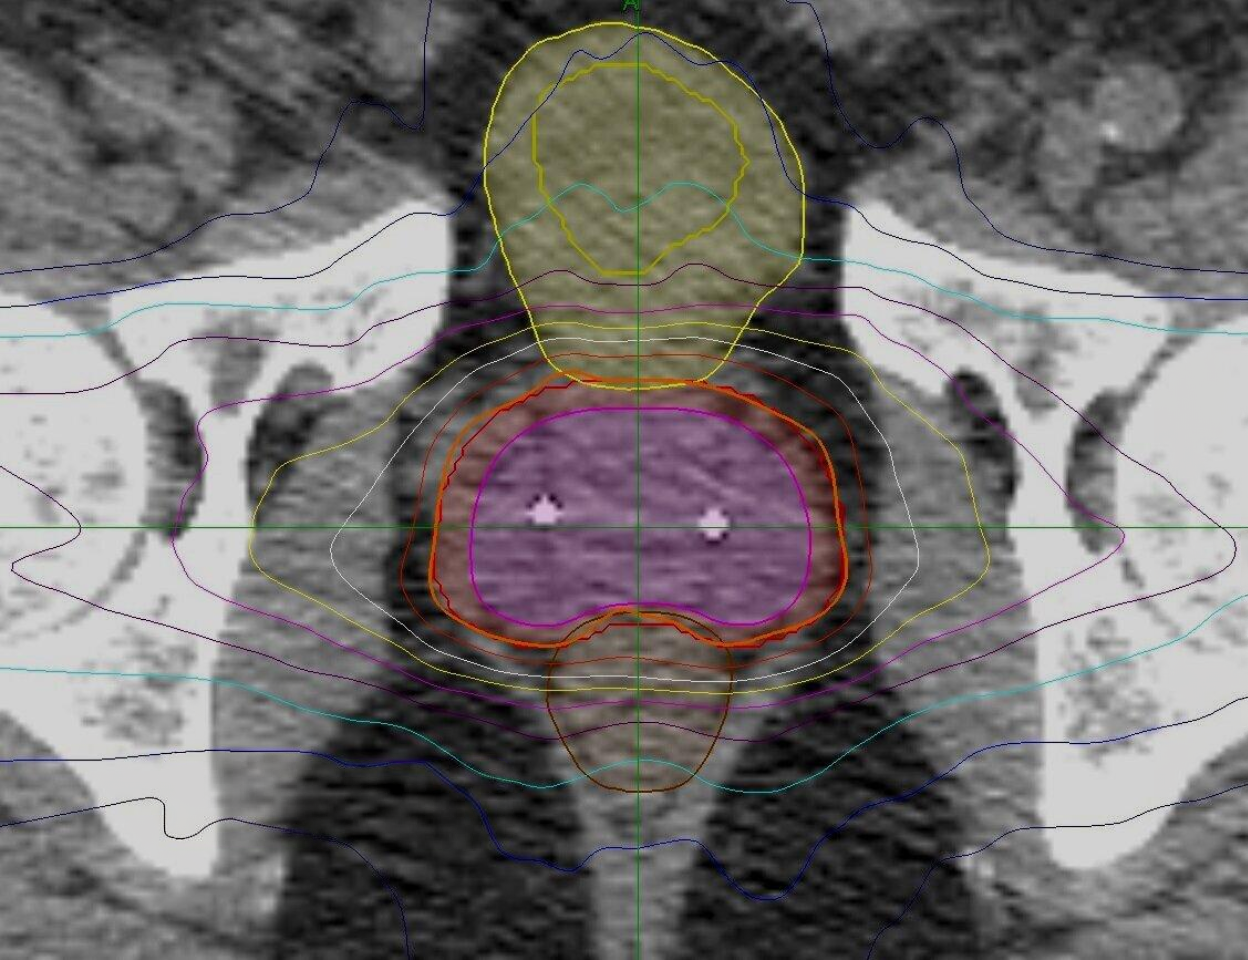

Contouring, Treatment Plan Evaluation, Fiducial and Hydrogel Assessment

hydrogelplcmtn1.jpg